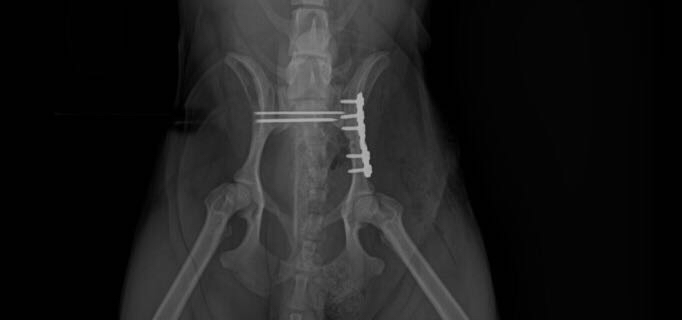

犬骨盆骨折内固定

犬骨盆骨折,多数情况是由于车祸导致,此图中的骨折犬就是 由于未拴犬链,被汽车撞伤,导致左侧髂骨体骨折,右侧见髂关节脱位,术后两个月恢复正常做了,所以动物主人遛狗时一定拴好犬链。